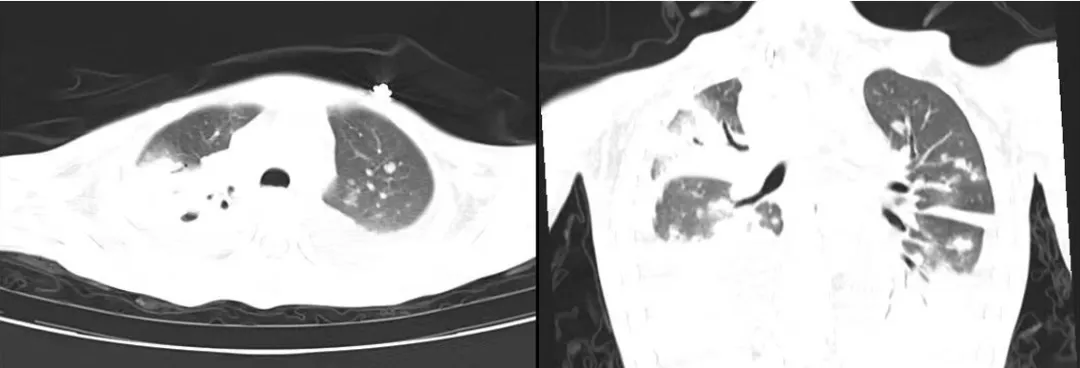

术后的全面检查,最终证实了小月的病因——结核感染。胸部CT显示,她的双肺布满白块,还伴有多个坏死空洞。感染科主任黄丽素推测,结核菌最初潜伏在小月肺部引发反复咳嗽,随后通过血液和淋巴系统全身扩散,在腹腔淋巴结“扎根”后攻击肠道,进展为肠坏死、肠穿孔,若送诊再晚一步,肠道穿孔引发的一系列休克、多脏器功能衰竭,可能就直接夺走了孩子的生命。

肺部多发斑块影、累及多肺叶伴胸腔积液、肺空洞